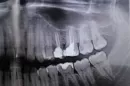

Что это может быть? Вот на всякий случай снимок, делали до лечения (предпоследний сверху зуб).

Кажется мне, что у Вас периодонтит 27 зуба! На снимке заметна крупная кариозная полость. Возможно, нерв был поражен и инфицирован давно, и не стоило ставить пломбу, лечить зуб, как глубокий кариес. Возможно, зуб уже был при хроническом пульпите или даже хроническом периодонтите. Попытки сохранить нерв только затянули время, а возможно, припухлость была не только от десны, поэтому вполне вероятно и развился одонтогенный гайморит.

Дело в том, что гайморит теперь без лечения зуба не пройдет, только притихнет от лечения. Надо постараться вылечить корни 27 зуба. Но, возможно, верхушки его находятся внутри гайморовой пазухи — бывает такое строение организма, в таком случае шансов на сохрание зуба мало. Надо сделать компьютерную томографию, будет все ясно.